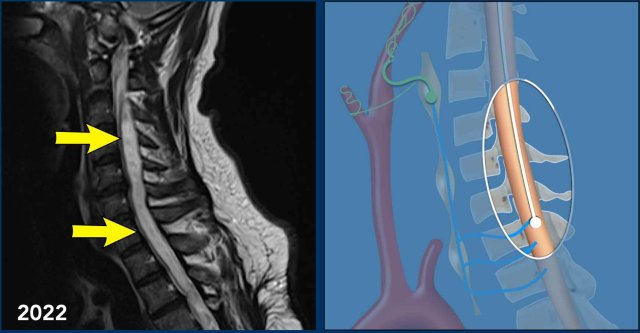

These images are of a 45-year old man who had a traumatic cord injury at the level of T4-5 some years ago.

He now presents with progressive pain in the legs with decreased reflexes in both arms and legs and a bilateral Horner.

Sagittal T2 TSE weighted images in 2021 of the cervicothoracic spine show loss of height of verterbra T4 with cord dissection and a cystic myelomalacia at this level and surrounding syringohydromyelia.

In 2022 sagittal T2W images of the cervicothoracal spine show progressive syringohydromyelia.

The Horner syndrome can be explained by the progressive syringohydomyelia at the cervical level with disruption of the first order neurons of the oculosympathetic pathway.